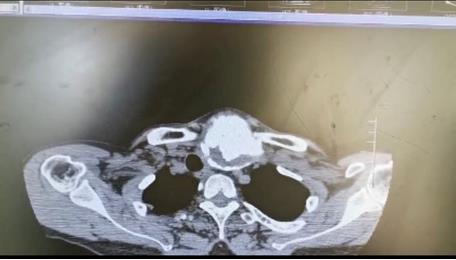

患者朱女士,68歲,頸部包塊呈進(jìn)行性增大50年,來院后彩超及CT提示左側(cè)甲狀腺腫瘤已經(jīng)超過10公分并邊緣鈣化,氣管移位較明顯,腫瘤較大屬于罕見,不僅給患者造成心理陰影,還影響了正常生活,偶有憋悶不適,進(jìn)食較大食物感哽咽不適。流動醫(yī)院下鄉(xiāng)義診時(shí),發(fā)現(xiàn)包塊已經(jīng)很大了,影響到頸部的活動及飲食。醫(yī)生與患者及家屬溝通講解病情,表示我們?nèi)揍t(yī)院能治療。最后患者及家屬抱著試一試的態(tài)度來到延安大學(xué)咸陽醫(yī)院。

因逐漸長大的頸部嚴(yán)重影響飲食及活動,長達(dá)50年的折磨,患者身體很瘦、體質(zhì)差。甲狀腺腫瘤,瘤體大,手術(shù)創(chuàng)面較大,損傷喉返神經(jīng)及甲狀旁腺風(fēng)險(xiǎn)高,術(shù)后可能出現(xiàn)聲音嘶啞及低鈣抽搐等嚴(yán)重并發(fā)癥。同時(shí)瘤體長期對氣管的壓迫,致術(shù)后可能出現(xiàn)氣管軟化而發(fā)生致命性并發(fā)癥。